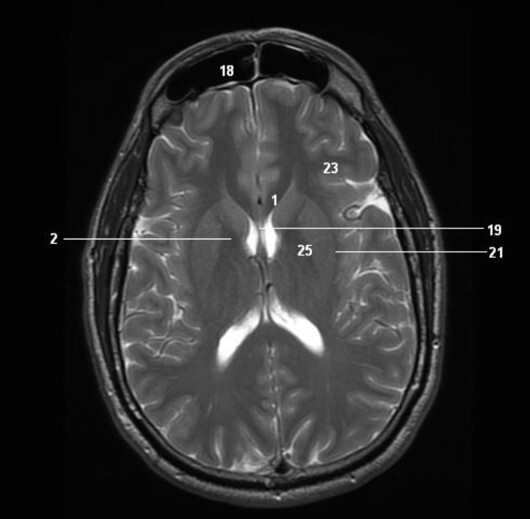

12

Q

Label 2,18,19,21

A

2=Rt internal capsule

18=Frontal sinus

19=Septum pellucidum

21=Lt external capsule